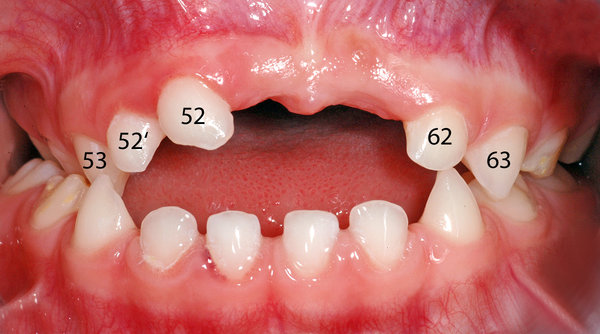

- Überzähliger seitlicher Milch-Schneidezahn rechts (52'); siehe dazu auch den Beitrag zu überzähligen Zähnen.

- Kreuzbiss im Seitenzahnbereich auf der rechten Seite (blaue Pfeile im Bild).

- Offener Biss in der Front (das heisst, dass die Schneidezähne beim Zusammenbeissen nicht «übereinander» oder aneinander kommen; ist im Bild blau markiert).

- Ansicht von vorne, Zähne nummeriert